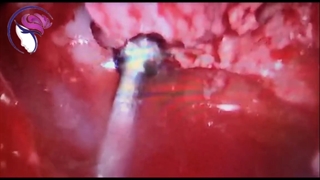

فیلم آندوسکوپی درمان نشت مایع مغزی نخاعی